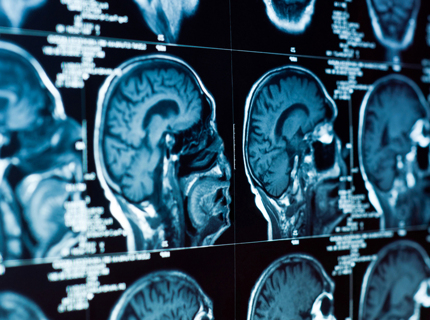

В мозге обнаружен скрытый ритм, повышающий интеллект

Названа особенность мозга людей с высоким интеллектом